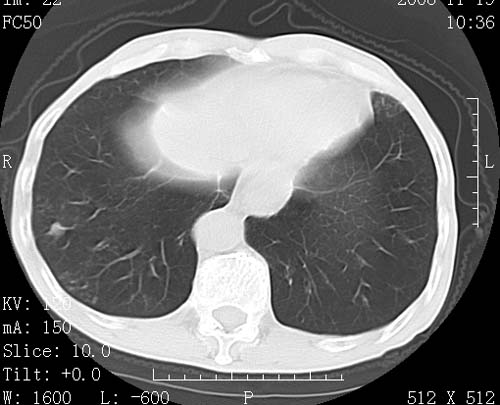

标题: CT16691:m 67 胃镜确诊食管下段及贲门癌 [打印本页]

标题: CT16691:m 67 胃镜确诊食管下段及贲门癌

术前查体,双肺部结节是转移?结核?请点评

1)符合食管癌表现。2)两肺及纵隔淋巴结多发性转移瘤。3)左肺上叶舌段及两肺下叶炎症感染。

食管癌伴双肺转移,评述:肺部毛细血管网丰富,全身血液均快速流经肺部,癌细胞容易过滤定植,形成转移瘤,影象特点为以毛细血管末梢为中心的结节灶,边缘光滑锐利,少见有中心空洞着,不同来源的转移瘤可有各自特点,如甲状腺癌为双肺弥漫性微结节,本例有原发灶,双肺影象灶典型,左肺舌段条带状网格样伴胸膜天幕征,可视为癌性淋巴管炎。